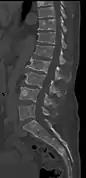

Illustration showing the most common site of bone lesions in vertebrae

Bone pain affects almost 70% of people with multiple myeloma and is the most common symptom.[15] Myeloma bone pain usually involves the spine and ribs, and worsens with activity. Persistent, localized pain may indicate a pathological bone fracture. Involvement of the vertebrae may lead to spinal cord compression or kyphosis. Myeloma bone disease is due to the overexpression of receptor activator for nuclear factor κ B ligand (RANKL) by bone marrow stroma. RANKL activates osteoclasts, which resorb bone. The resultant bone lesions are lytic (cause breakdown) in nature, and are best seen in plain radiographs, which may show "punched-out" resorptive lesions (including the "raindrop" appearance of the skull on radiography). The breakdown of bone also leads to the release of calcium ions into the blood, leading to hypercalcemia and its associated symptoms.